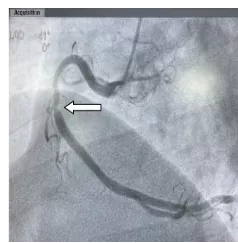

陈某术前-右冠重度狭窄

为了更精准了解管腔病变情况,经过由中国科学院科技服务网络计划重点项目自主研发的OCT检查后,发现刘某前降支中段狭窄处斑块负荷严重,斑块薄层纤维帽,存在脂质池,有随时发生破裂可能,管腔面积最小处仅为1.07mm2,提示血管严重狭窄。陈某右冠中段存在破裂斑块,与家属商议后,决定给予支架干预治疗。